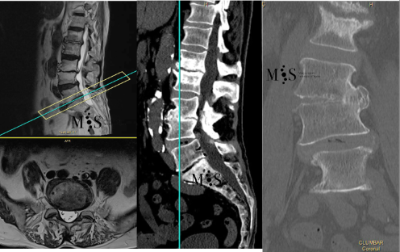

Scoliosis is a deformity/curving of the spine in the frontal plane. It can be congenital (present since birth) or degenerative (developed during the aging process). Progressive degeneration of the intervertebral disks (because of age, weight, activity, etc.) can lead to the spine to deform and curve in, ending up as a degenerative scoliosis, also called "de novo" because it is of "new" appearance in comparison to congenital scoliosis which has been present since birth.

Scoliosis lead to a curved back with the patient having problems walking with a straight back, and it can lead to an intense back pain. The spinal deformity and curving can lead to an impingement of the nerve roots which can cause radiating leg pain.

In these painful cases, surgery is indicated to (partially) correct the deformity and mainly to reduce/eliminate the pain generated by the scoliosis. In the most severe scoliosis cases an osteotomy (chiseling of a vertebral bone) may be required to straighten up the spine and reduce its deformity.

At the Morgenstern Institute of Spine we use the most advanced surgical endoscopic and percutaneous techniques to correct the degenerative scoliosis and speed up the patient’s recovery time. Hospital discharge is usually just a few days after surgery.